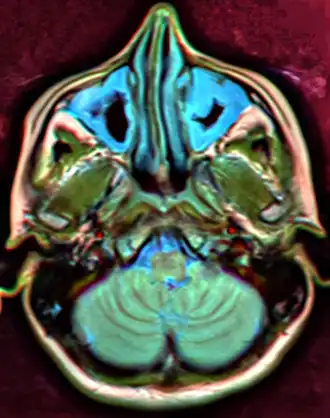

Illustration depicting sinusitis, note the fluid in the sini

Sinusitis (or rhinosinusitis) is defined as an inflammation of the mucous membrane that lines the paranasal sinuses and is classified chronologically into several categories:[64]